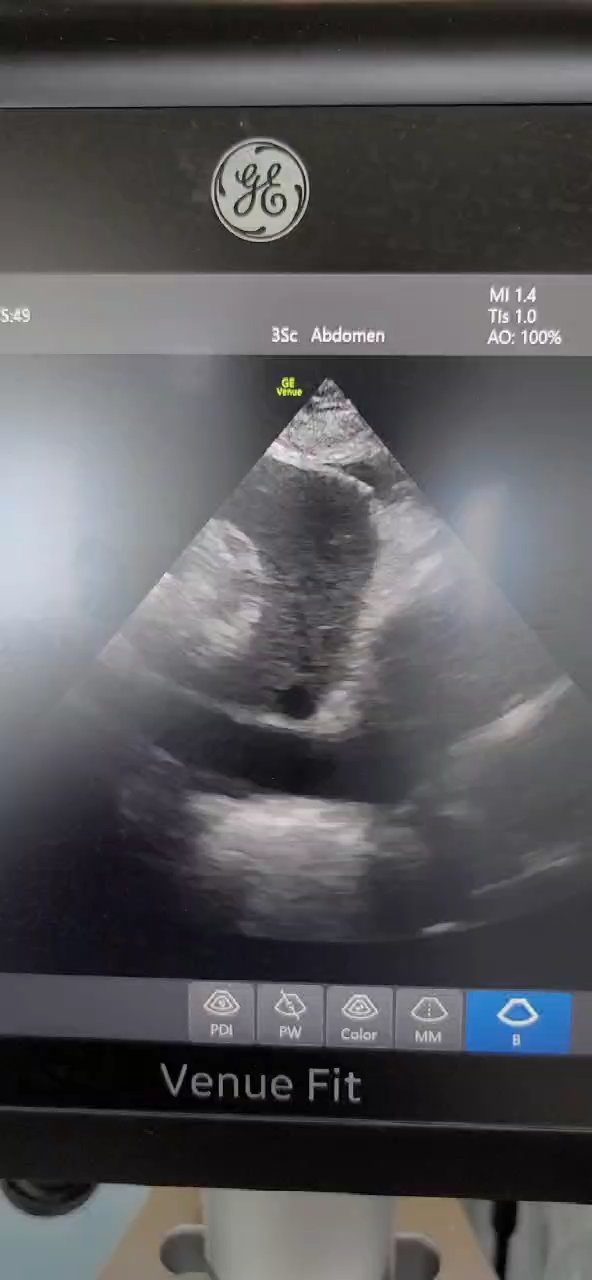

心脏超声:EF 48%,左心功能减低,左室壁各节段运动稍减低。二反、三反、主反(均少量)。下腔2.46cm,变异度0。

5.01 15:30 心脏超声:EF 65%,室壁运动未见明显异常。二反、三反、主反(均少量)。

下腔

5.02 17:00 动脉血气:pH 7.35,pO2 90,pCO2 38,FIO2 60%,乳酸 3.7,BE -4.2、电解质正常。心率108次/分,呼吸频率16次/分,脉氧99%,血压 117/64mmHg(去甲2.0ug/kg.min,肾上腺素0.01ug/kg.min,脉博有力)。下腔2.07cm。

5.03 10:00 动脉血气:pH 7.46,pO2 87,pCO2 35,FIO2 60%,乳酸 3.2,BE 1.4、电解质正常。血常规 白细胞11.25*10^9/L,血红蛋白103g/L,血小板23*10^9/L,中性粒细胞百分比95.7%,嗜酸性粒细胞百分比0.0%,淋巴细胞绝对值 0.27*10^9/L,CRP 156.33mg/l。凝血功能 D-二聚体2.56mg/L,PT 11.2秒,APTT 38.3秒。生化全套 肾功能电解质正常,ALT 52U/L,AST 140U/L,总胆红素41.1umol/l,直接胆红素 23.3umol/L,间接胆红素、碱性磷酸酶正常,白蛋白34.4g/L。N末端B型脑钠肽前体 4815.9pg/ml。降钙素原 44.23ng/ml。心率109次/分,呼吸频率17次/分,脉氧98%,血压 147/84mmHg(脉博强)。心脏超声较前相仿,下肢血管B超无血栓。CTPA未见肺栓塞。双肺感染。